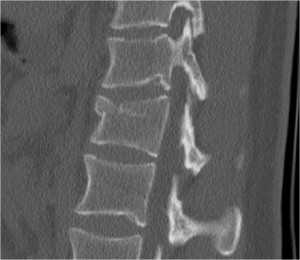

Диагноз подтверждается результатами рентгенографии в переднезадней и боковой проекции. При подозрении на нестабильный перелом позвоночника проводят КТ (компьютерную томографию), которая позволяет увидеть как переломы костей, так и повреждения мягкотканных структур. Для диагностики повреждений корешков и спинного мозга используют МРТ позвоночника.

КТ грудного и поясничного отделов позвоночника. Перелом поперечного отростка 2-го и 3-го поясничного позвонка без смещения.

Компрессионные переломы видны при рентгенографии, однако уже при наличии заметной клиновидности. На КТ лучше видны дефекты замыкательной пластинки. МРТ позвоночника отличается возможностью определять «свежие» компрессионные переломы, сопровождающиеся нарушением трабекул и отеком костного мозга.

КТ, реформация в сагиттальную плоскость. Клиновидность и нарушение замыкательной пластинки.

КТ. Реформация в сагиттальную плоскость. Компрессионные переломы позвонков поясничного отдела.